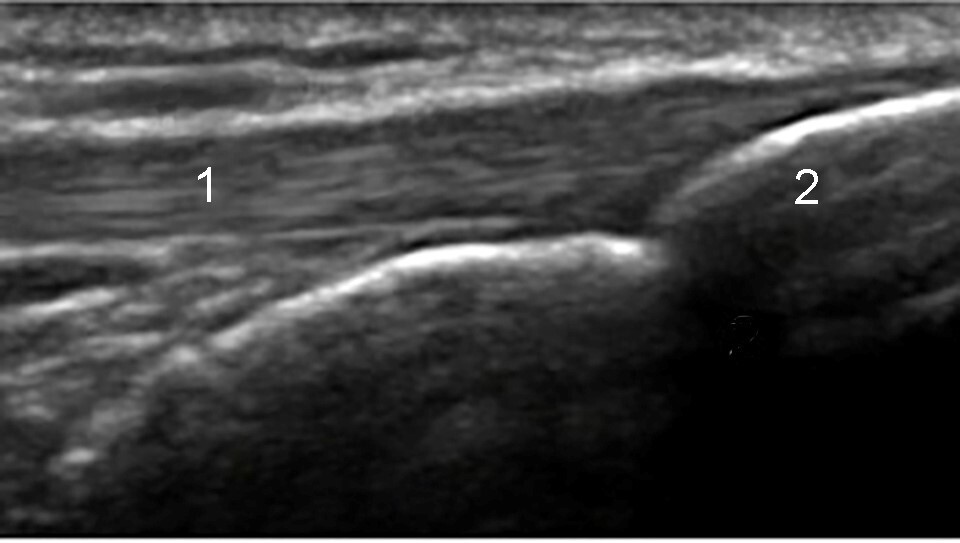

Imagen de la tuberosidad tibial de la rodilla

Tendón rotuliano

Tuberosidad tibial